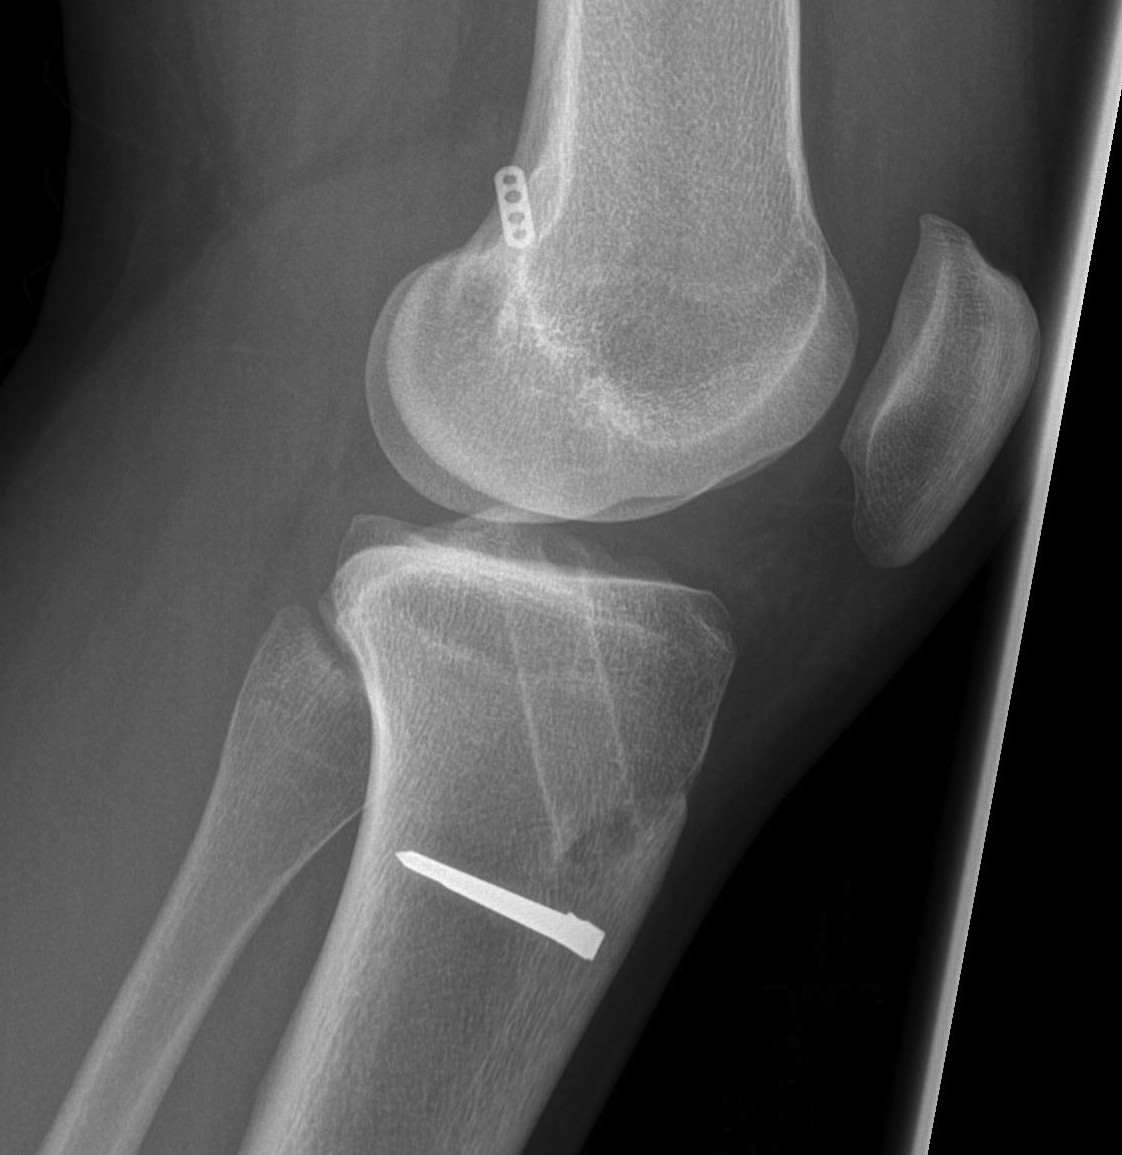

Tibial Tunnel

More forgiving

Ideal Tibial tunnel placement

- posterior and parallel to the tibial intersection of Blumensaat's line in full extension

- this will prevent it impinging on the notch

A. Anterior placement

- increases tension in flexion

- may result in notch impingement in extension

- stretching of graft

B. Posterior placement

- causes PCL impingement

- reduces the graft's ability to control AP translation

C. Lateral placement

- causes impingement on the medial wall of the lateral femoral condyle